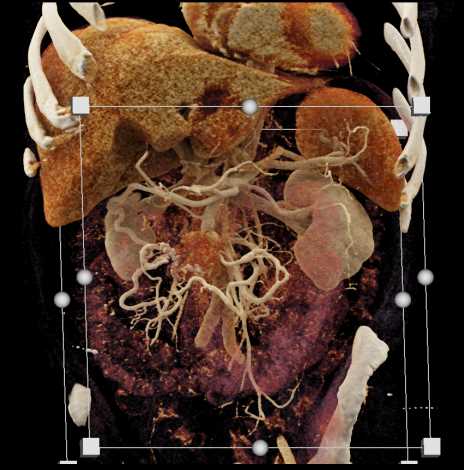

Carcinoid Tumor with Desmoplastic Reaction